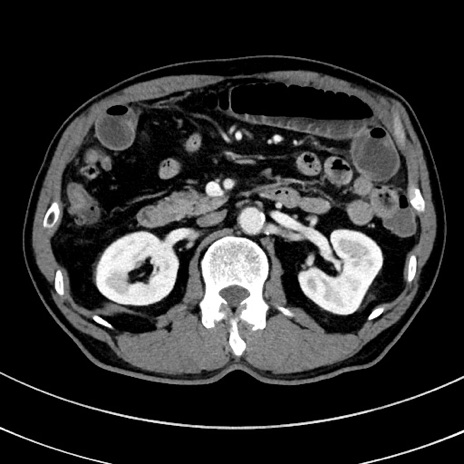

冠状断像

【症例】 60歳代男性

【主訴】 黒色吐物

【現病歴】 4日前から嘔気自覚、2日前の朝食後にも嘔気あり、自分で手で嘔吐反射起こし嘔吐したところ血が混ざっていたため受診。

【既往歴】 5年前汎発性腹膜炎を伴う急性虫垂炎で手術、高血圧、前立腺肥大症、高脂血症

【身体所見】 腹部正中に手術癩痕あり 腹部平坦・軟圧痛なし膨満感あり

【データ】WBC 8400、CRP 4.54